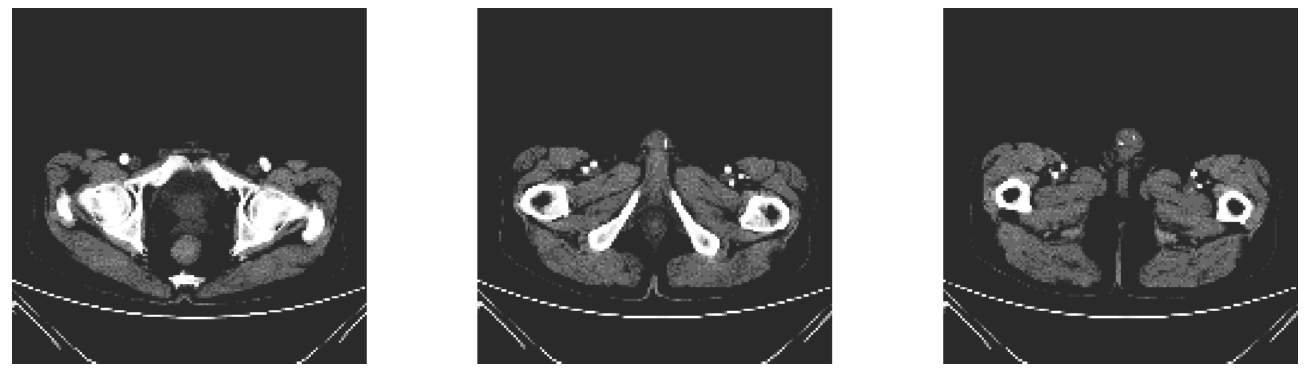

数字图像处理技术具有直观性、无创伤、安全方便等优点,在医学领域有着非常广泛且重要的应用。利用电磁波谱成像分析系统诊断病情,如:显微镜图像分析、DNA成像分析等;CT、B超、血管造影、红外乳腺、显微病理、电子显微镜、远程医疗图像、皮肤图像、X射线、γ刀与χ刀脑外科等都离不开图像,通过三维测量可视化软件系统还可对各类医学断层图像进行分析处理,提供诊断依据。如图1-9所示为人体组织CT图像,通过数字图像处理技术检测病变部位,可以提高医疗诊断的智能化。

图1-9 人体组织CT图像